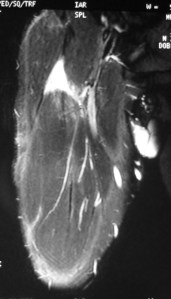

The Sports Physician referred him for an MRI scan.

The MRI scan showed a rupture of the proximal rectus femoris musculotendinous junction.

A bedside ultrasound scan in my clinic reviewed a completely torn rectus femoris and the torn end was still in the proximal third of his right thigh: